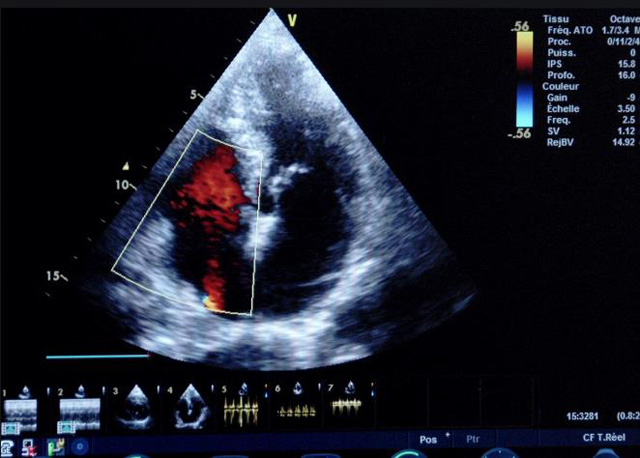

二、彩色室壁運動分析

(一)基本原理彩色室璧運動分析,從整體散射數(shù)據(jù)中識別心內(nèi)膜邊界,并與前一幀彩色不同,心臟收縮或舒張期開始到結(jié)束時心內(nèi)膜的全部過程。每一次順序顯示結(jié)束后,原來的彩色自動消失,以便進入下一個顯示過程。其結(jié)果是獲得對應于每一個心動周期的彩色顯示,描繪特定周期內(nèi)室壁運動的時間運動軌跡。

(二)操作步驟根據(jù)背向散射數(shù)據(jù)中將心內(nèi)膜運動的位移過程分類為組織或血液的原理,邊緣檢測跟蹤心內(nèi)膜和血液的界面。橙色表示收縮期的開始,收縮期不同時相逐幀顯示色彩均疊加在收縮末期最后一幀圖像中。檢查時,可按以下步驟進行:

①顯示較為理想的二維圖像,常用切面有心尖四腔心、二腔心、左心室長軸和左心室乳頭肌水平短軸切面。

③啟動CK系統(tǒng),啟動后劃定感興趣區(qū)域。同時記錄的心動圖R波頂點為舒張末期,T波終點為收縮末期,顯示RT間期的CK彩階圖,連續(xù)記錄3~ 5個心動周期。

(三)檢測節(jié)段性室壁運動異常,研究冠心病患者左心室功能和分析局部室壁運動過程中。測量每一節(jié)段室壁的運動量,運動正常的節(jié)段彩帶色彩均勻?qū)哟喂庹?。運動減弱的節(jié)段,厚度薄層次不全。心內(nèi)膜位移幅度和速度均減低。心內(nèi)膜位移幅度和速度甚低或難以測得。正常的多層彩帶消失,呈現(xiàn)紅色色帶,心內(nèi)膜位移呈負向,幅度和速度亦減低。急性心肌梗死的患者中可用于識別存活心肌抑或壞死心肌。多巴酚丁胺負荷試驗存活心肌的心內(nèi)膜位移幅度增高,停藥后即消失,而壞死心肌則無上述表現(xiàn)。實時檢查冠心病的節(jié)段性室壁運動異常,有時候通過發(fā)現(xiàn)局部心肌運動的時相異常,對于心臟傳導障礙的診斷也可能有幫助。